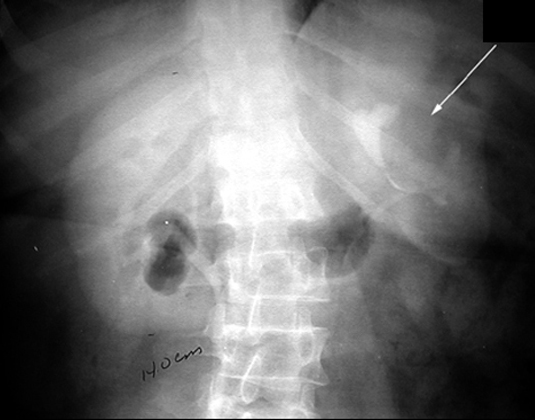

Spine x-ray shows severe osteoarthritic changes of lower lumbar spine. Incidentally there is a soft tissue mass overlying left renal area. Workup of this incidental mass turned out to be Simple Renal cyst.